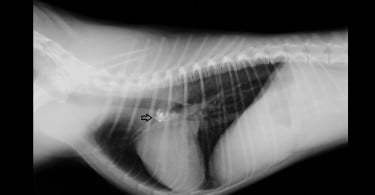

A iniciativa contempla três workshops, que decorrem em simultâneo nas instalações da FMV-UTL, subordinadas aos temas: Pequenos Animais (Medicina e Cirurgia Respiratória), Equinos (Diagnóstico e Tratamento de Claudicações) e Bovinos (Gestão de uma Exploração de Bovinos).